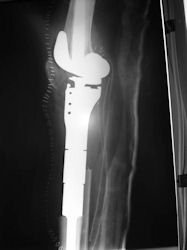

Examples of radical limb sparing surgeries for osteosarcomas in various anatomic locations (distal femur, proximal tibia, proximal humerus, scapula)

In each case, the tumor and bone from which it arose were resected. This required meticulous dissection, mobilization and preservation of adjacent pertinent neurovascular structures. In each case presented here, the defect was reconstructed with a special modular segmental tumor prosthesis. This also replaces the adjacent joint in many instances.

| Limb-sparing surgery for osteosarcoma of distal femur – Plain Xrays |

| Proximal Tibia Osteosarcoma: Limb-Sparing Surgery |

Postoperative X-Rays